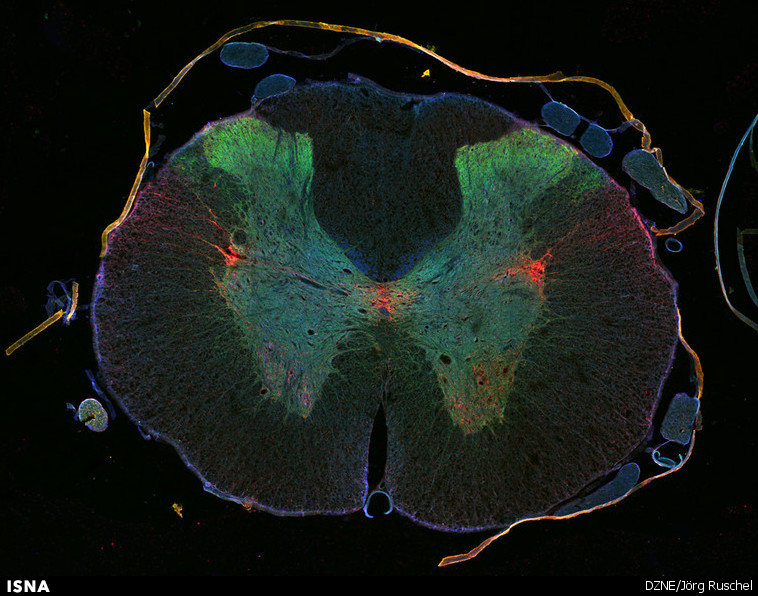

مدتهای زیادی است که ضایعات نخاعی و عصبی عارضهای غیرقابل برگشت و درمانناپذیر محسوب میشوند، اما محققان دانشگاه دارتموث به تازگی روشی برای سنتز محصولات کمیاب طبیعی طراحی کردهاند که بازیابی و رشد دوباره سلولهای عصبی آسیبدیده را امکانپذیر میکند.

هم اکنون محققان دارتموث واکنشهای شیمیایی را کشف کردهاند که میتواند برخی از نیرومندترین و کمیابترین اعضای خانواده این محصولات مفید را تولید کند. نتایج مطالعات آزمایشگاهی آنها نشان میدهد که روش جدید در آمادهسازی محصولات طبیعی درمانکننده ضایعات نخاعی میتواند منجر به تشکیل کربوکسیلیکهای مورد نظر و سنتز محصولات طبیعی شود. این محققان با کشف یک فرآیند واکنشی آبشاری، سازوکار لازم برای سنتز آزمایشگاهی این ترکیبات پیچیده را به دست آوردهاند.

این موفقیت جدید مسیر سنتزی منحصربهفردی ارائه میدهد که میتواند برای تولید آنالوگهای سنتزی که پیش از این به سادگی امکانپذیر نبود، مورد استفاده قرار بگیرد و روش جدیدی برای درمان ضایعات نخاعی پیش روی محققان قرار دهد.